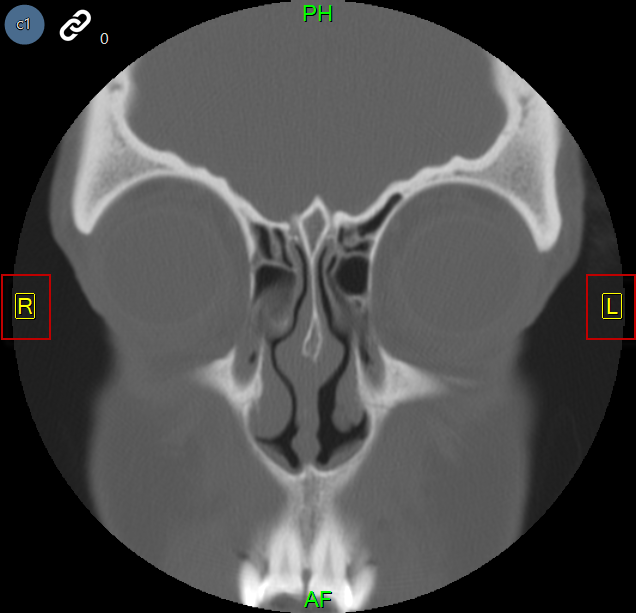

Az alábbi képek egy orrmelléküregi CT-t és egy mammográfiát ábrázolnak, amelyen automatikus orientáció van alkalmazva.

Az automatikus orientáció funkció felülírja a modalitás által meghatározott alapértelmezett betegorientációt, és a felhasználó által meghatározott orientációt alkalmaz. Ha egy képen automatikus orientációt alkalmaznak, a beteg orientációs mutatói kényszerítetten a képen, sárga színnel jelennek meg.